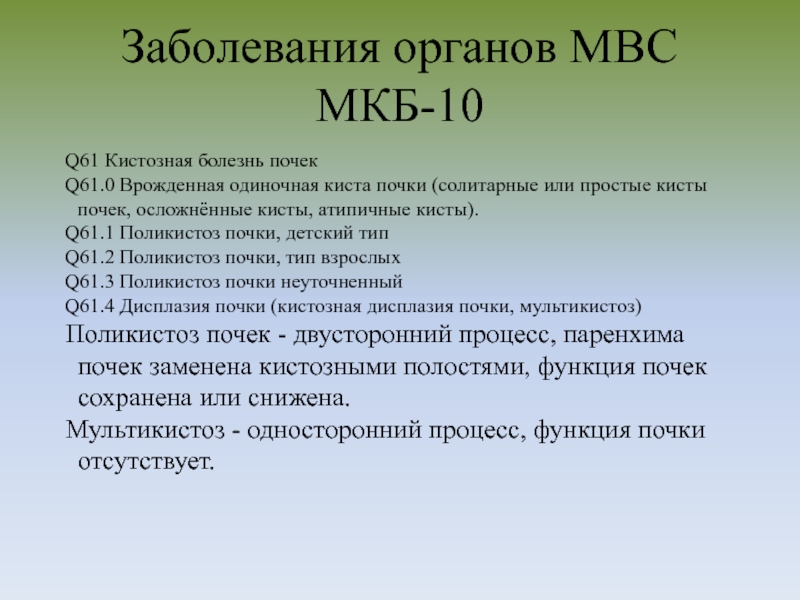

Острая внебольничная пневмония по МКБ-10: признаки и примеры